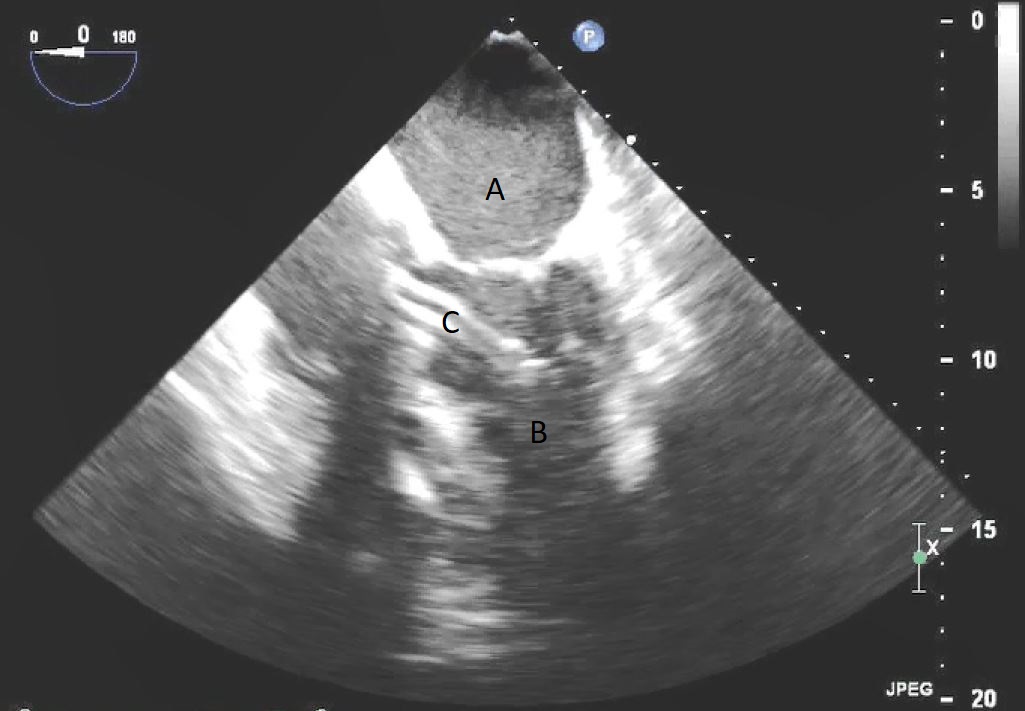

Fig. 5.A midesophageal 4 chamber view on TEE demonstrating an Impella traversing the aortic valve with the inflow port in the left ventricle. (A) Left Atrium. (B) Left Ventricle. (C) Impella.